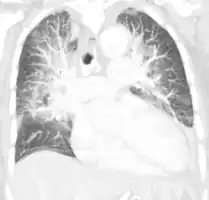

Acute pulmonary edema on CT

Pulmonary edema on CT-scan (coronal MPR)